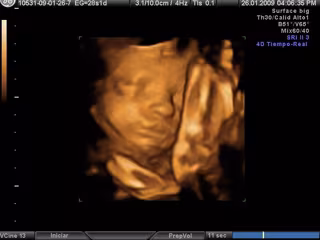

Ecografía en 3D- embarazo

La osteoporosis afecta al 35 por ciento de las mujeres de más de 52 por ciento y hasta el 52 por ciento de las mayores de 70 años, pero su prevención puede empezar durante la etapa fetal, según el presidente electo de la Asociación Española para el Estudio de la Menopáusia (AEEM), Pácido Llaneza, que recomienda a las mujeres embarazadas llevar una dieta adecuada "para que los huesos del recién nacido se formen correctamente".